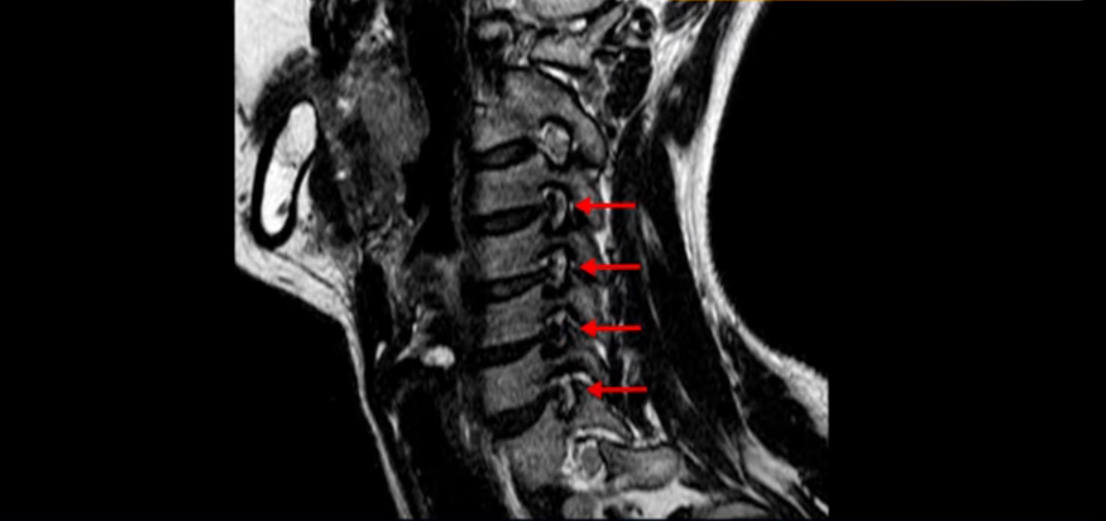

그런데 이분 목을 보시면 여러 마디의 뼈가 퇴행이 진행되어 있습니다. 뼈가 깍두기처럼 각지고 예뻐야 하는데 끝이 조금씩 변형되어 뾰족하게 자라고 있습니다.

이런 게 협착을 일으킵니다. 그래서 우선 오른쪽 신경구멍 즉 추간공을 살펴보면 맨 위의 한마디를 빼고는 다 좁아져 있습니다.

특히 5번 6번 구멍이 가장 좁습니다. 이걸 협착이라고 합니다.

목 치료가 쉽다고 하는 것은 이러한 근육치료가 허리에 비해 훨씬 더 쉬운 겁니다. 목 근육이 허리 근육에 비해 훨씬 구조도 단순하고 치료하기도 쉽습니다. 또 목은 머리만 받치고 있기 때문에 허리에 비해 부담을 적게 받습니다. 그래서 치료하기가 훨씬 더 쉽고 빠른 겁니다. 이분 목 X-RAY를 보면 일자목이면서 커브도 매우 좋지 않습니다. 이런 일자목, 거북목 상태에서는 목 주변 근육이 만성적으로 굳어있고 뭉쳐 있을 가능성이 매우 높고 그러니까 만성적인 목 통증이 있는 겁니다. 이런 뭉치고 굳어있는 근육이 목뼈를 심하게 잡아당기면 신경 자극 증상이나 신경 눌림 증상이 생기기 쉽습니다.